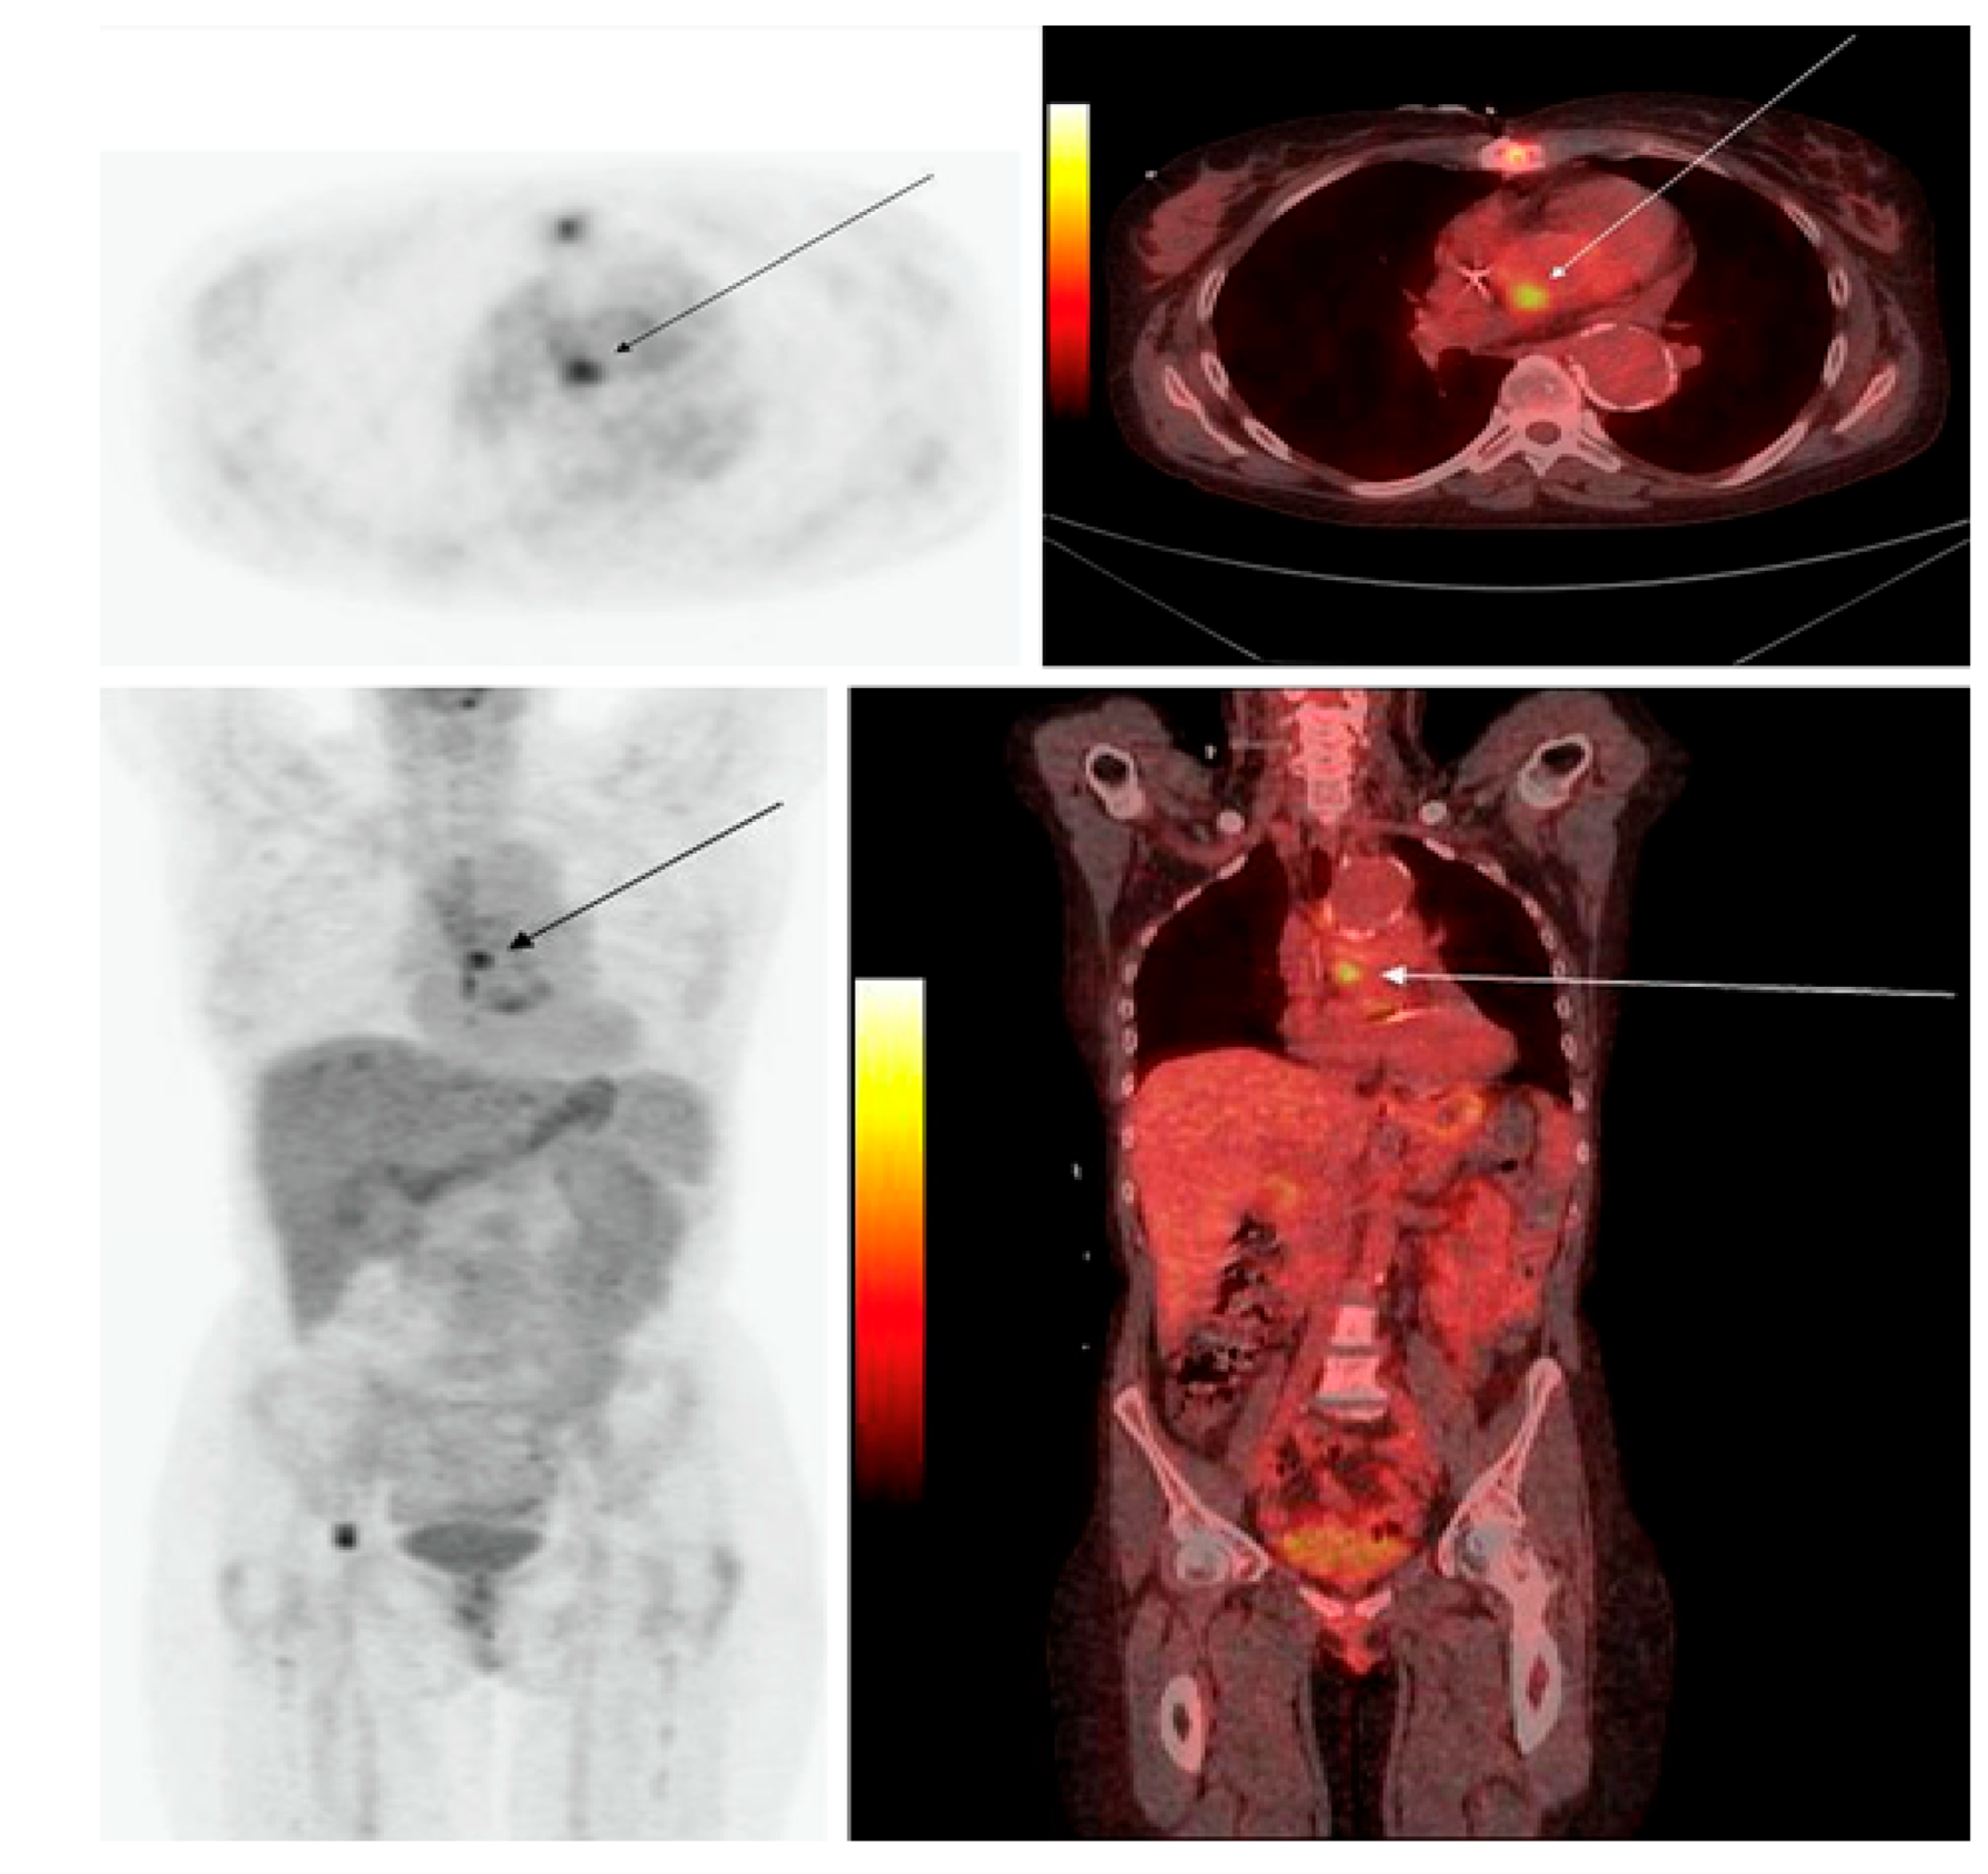

- Ordonez, A.A.; Wintaco, L.M.; Mota, F.; Restrepo, A.F.; Ruiz-Bedoya, C.A.; Reyes, C.F.; Uribe, L.G.; Abhishek, S.; D’Alessio, F.R.; Holt, D.P.; et al. Imaging Enterobacterales Infections in Patients Using Pathogen-Specific Positron Emission Tomography. Sci. Transl. Med. 2021, 13, eabe9805. [Google Scholar] [CrossRef]